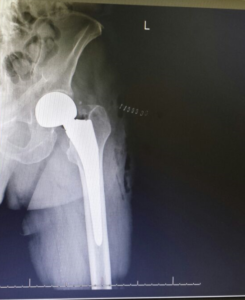

- Hip Fractures.

if the fracture is displaced, surgery may be needed to put the bone back into the correct position and fix the bone with Plates & screws or nails for adequate healing to occur.